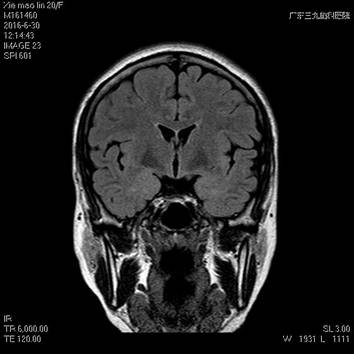

术前MR